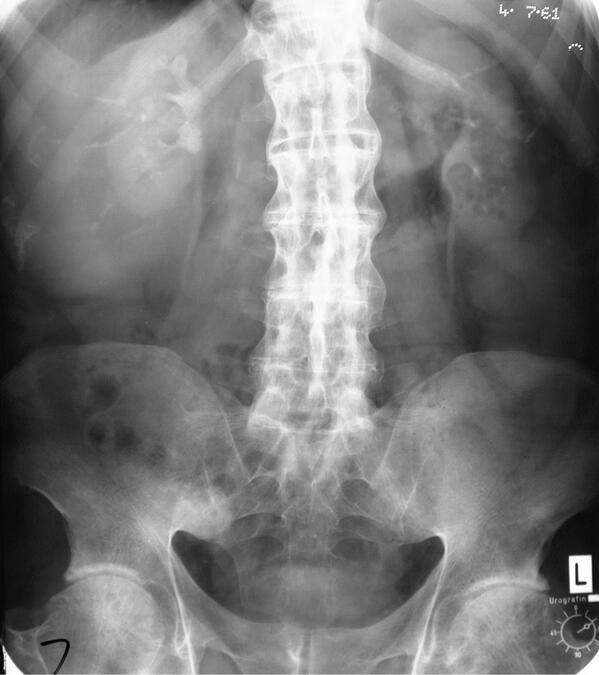

Bamboo Spine Vs Normal Spine . Together they form the spinal column. Flowing syndesmophytes are seen fusing the cervical spine vertebral bodies. Bamboo spine is a complication of ankylosing spondylitis, a chronic inflammatory condition that causes the spine to fuse and become rigid. Bamboo spine is a pathognomonic radiographic feature seen in ankylosing spondylitis that occurs as a result of vertebral body fusion by marginal syndesmophytes. The human spine is made up of 24 vertebrae (small bones) that run from the neck down to the lower back. Ankylosing spondylitis is a chronic seronegative autoimmune spondyloarthropathy characterized by bridging spinal osteophyte formation, enthesitis, sacroiliitis, and uveitis. Doctors call this advanced phase “bamboo spine.” you can feel a lot of pain in your back, stiffness, and soreness, which could limit.

Bamboo spine is a complication of ankylosing spondylitis, a chronic inflammatory condition that causes the spine to fuse and become rigid. Doctors call this advanced phase “bamboo spine.” you can feel a lot of pain in your back, stiffness, and soreness, which could limit. The human spine is made up of 24 vertebrae (small bones) that run from the neck down to the lower back. Flowing syndesmophytes are seen fusing the cervical spine vertebral bodies. Together they form the spinal column. Ankylosing spondylitis is a chronic seronegative autoimmune spondyloarthropathy characterized by bridging spinal osteophyte formation, enthesitis, sacroiliitis, and uveitis. Bamboo spine is a pathognomonic radiographic feature seen in ankylosing spondylitis that occurs as a result of vertebral body fusion by marginal syndesmophytes.